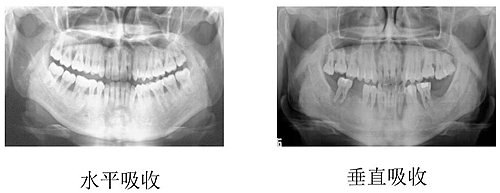

(一) 水平型吸收

是最常見的吸收方式。牙槽間隔、唇舌側(cè)或舌側(cè)的嵴頂邊緣呈水平吸收,而使牙槽嵴高度降低,通常形成骨上袋。

(二) 垂直型吸收

也稱角形吸收,指牙槽骨發(fā)生垂直方向或斜行的吸收,與牙根面之間形成一定角度的骨缺損,牙槽骨高度降低不多,而牙根周圍骨吸收較多。大多形成骨下袋,最常見于鄰面。根據(jù)骨質(zhì)破壞后剩余的骨壁數(shù)目,骨下袋可分為一壁骨袋、二壁骨袋、三壁骨袋、四壁骨袋、混合骨袋。

牙槽骨吸收的方式和程度,可通過X線片來觀察。正常情況下,牙槽嵴頂?shù)接匝拦琴|(zhì)界的距離約為1~2mm,若超過2mm則可視為牙槽骨吸收。牙周炎的骨吸收最初表現(xiàn)為牙槽嵴頂?shù)挠补虐逑?,或嵴頂模糊呈蟲蝕狀。